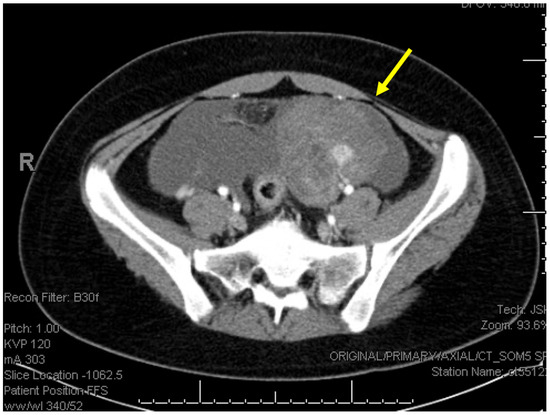

2. Detailed Case Description